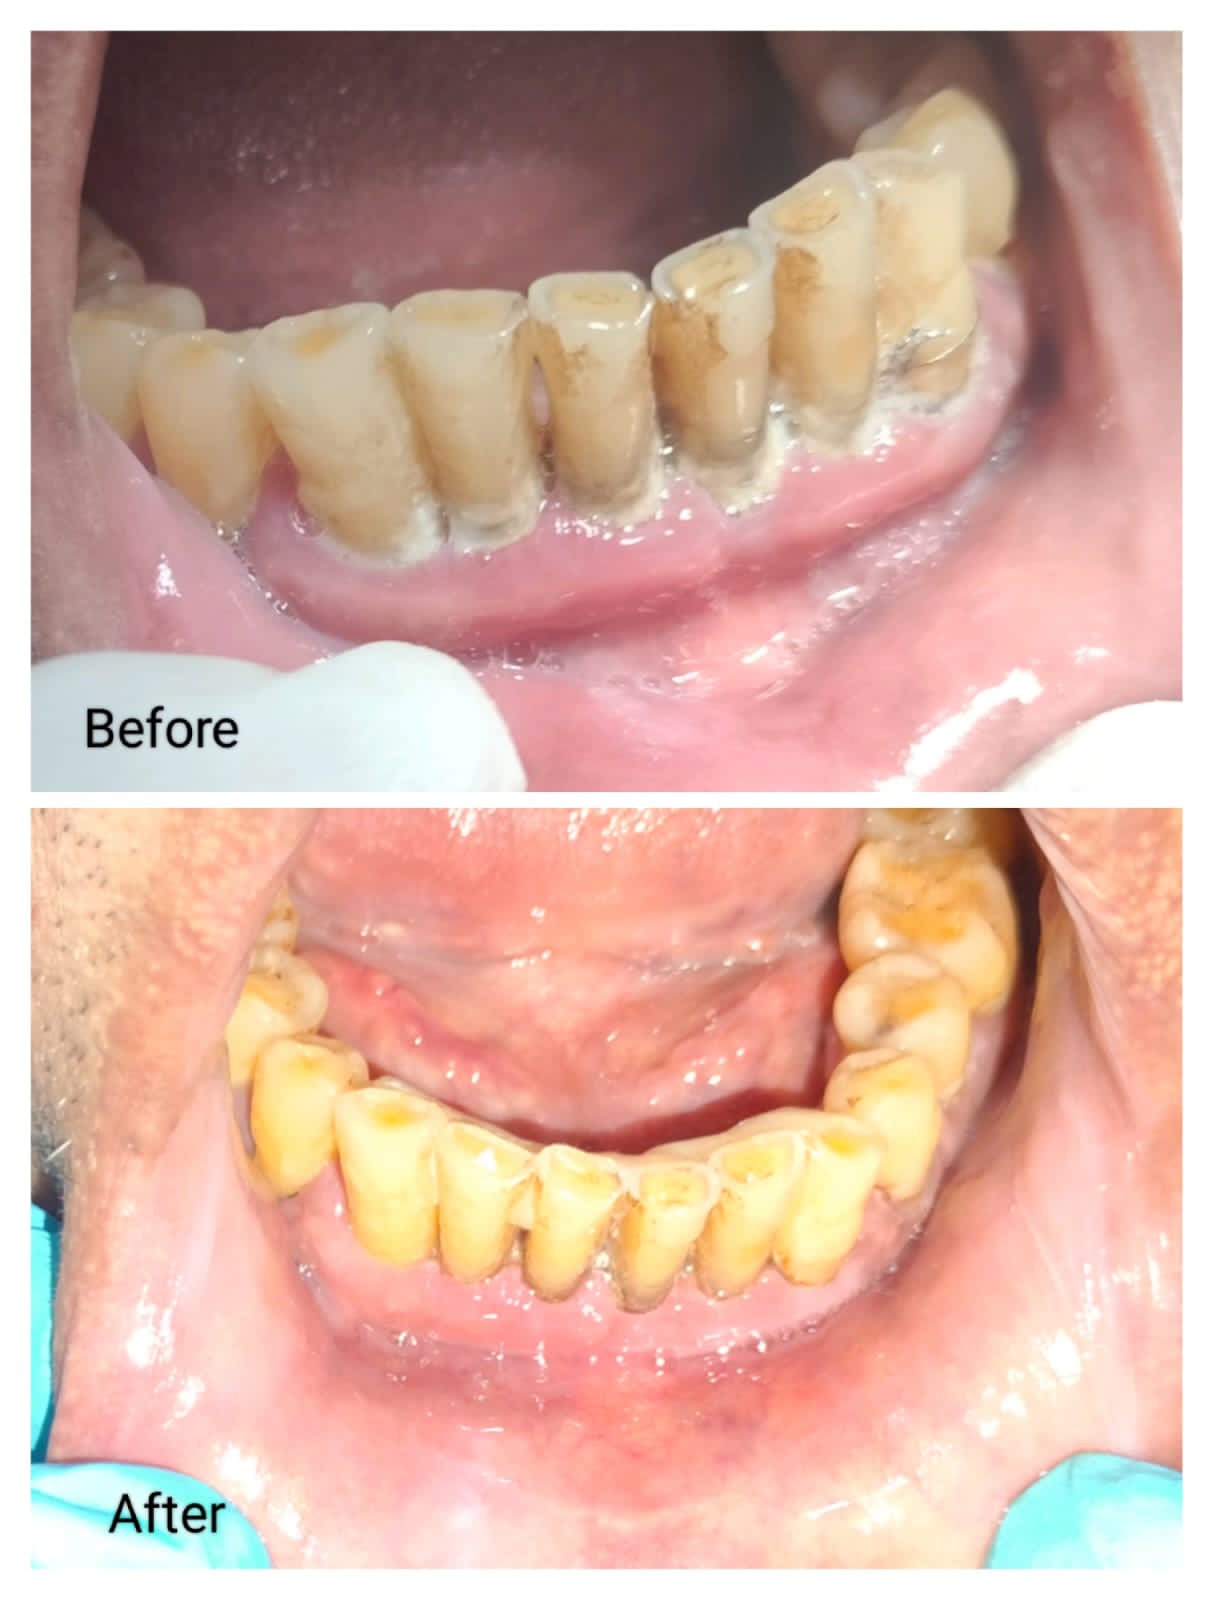

Image Gallery

Pictures That Speak